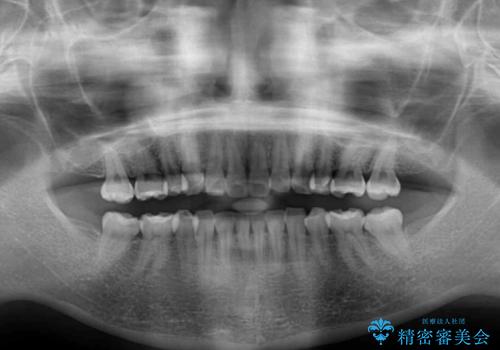

- 以前ワイヤー装置にて行った抜歯矯正の後戻りを気にして来院された患者様です。

前歯のデコボコにより、やや口元が突出した印象となっていたため、口元も引っ込めることとしました。

上下顎前歯に積極的にIPR(歯と歯の間を削る)を行い、インビザラインを用いて治療していくこととしました。